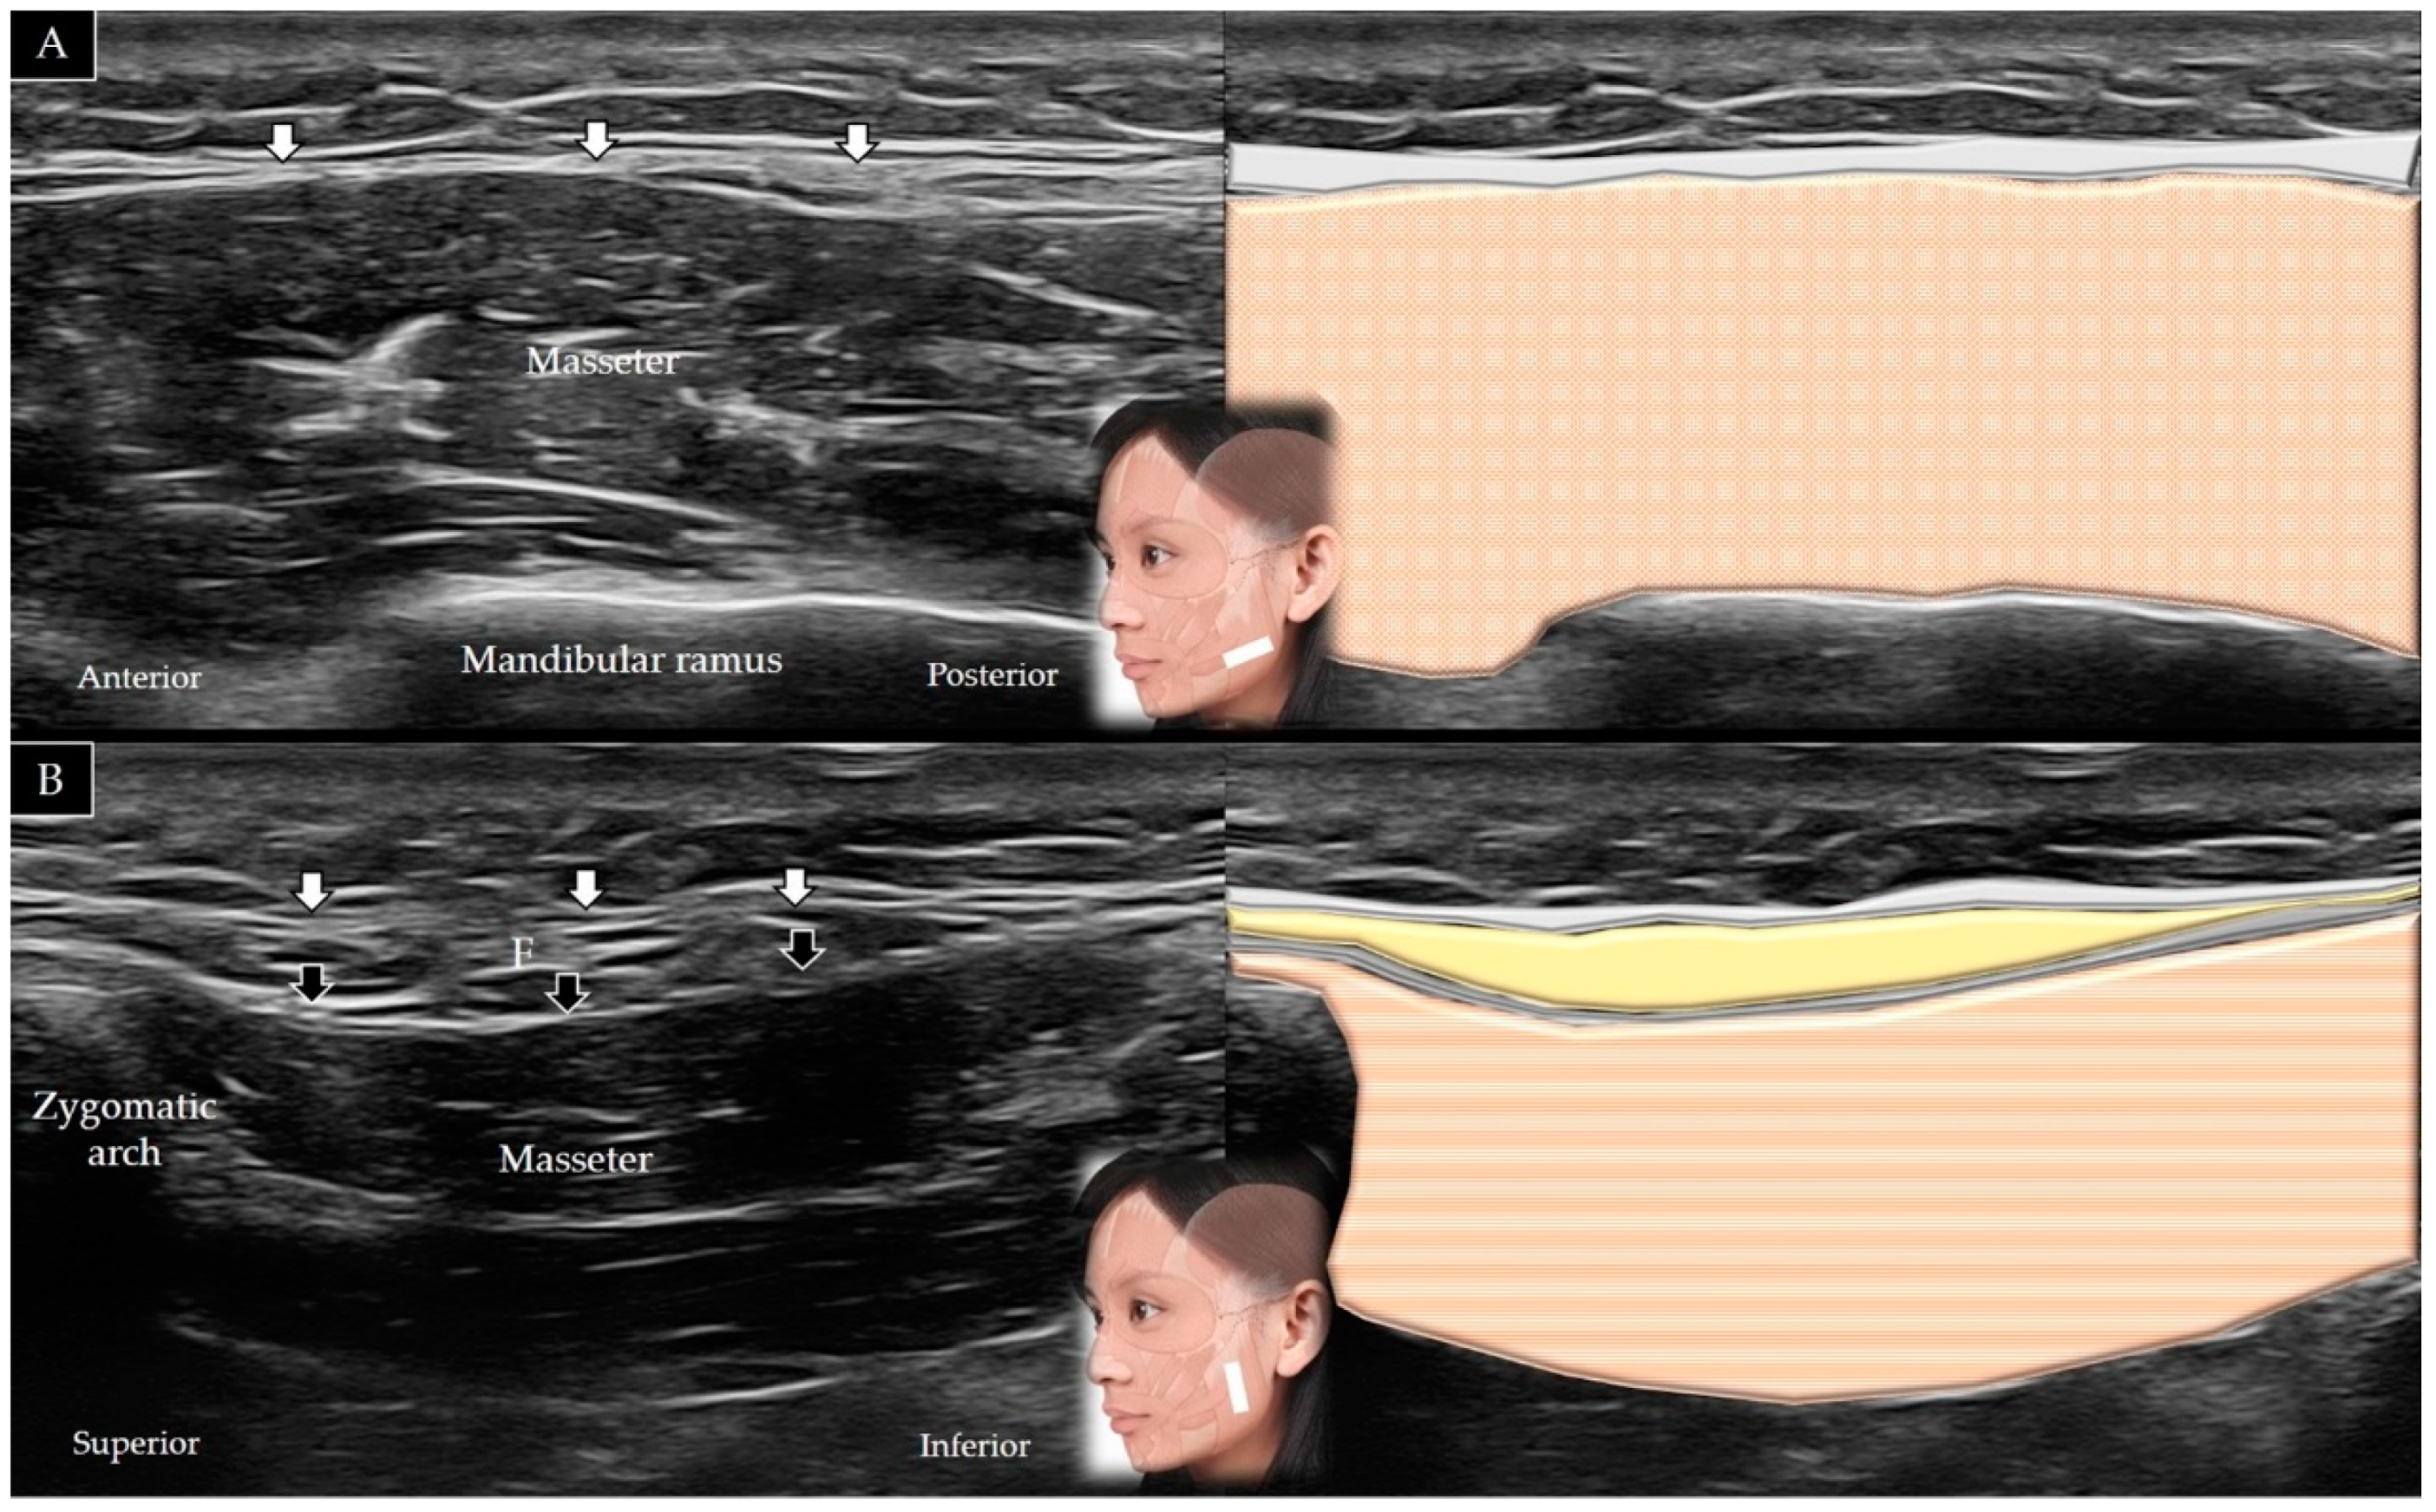

4.7. Masseter

4.7.2. Scanning Technique

| Masseter | Zygomatic arch | Mandibular ramus and angle | In the horizontal plane along the zygomatic arch, then moved caudally (short axis view) |